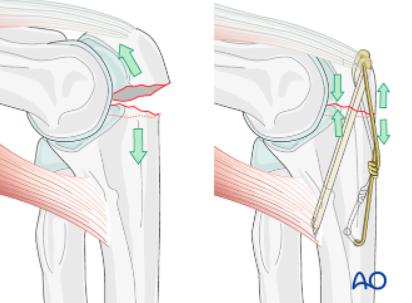

분쇄가 없는 가로방향 골절의 경우에는

Tension band wiring 을 이용하는 것이 치료의 gold standard

(표준 치료) 라고 할 수 있습니다.

Tension band wiring 방식의 수술은 벌어지려고 하는 골절부위의 힘을

8자 형태로 감은 철사를 통해 압박력으로 바꾸어 주는 힘을 이용하기 때문에

빠르게 재활을 할 수 있다는 장점이 있습니다.

골절선의 원위 4cm 되는 위치에 drill hole 을 뚫어 wire 를 8자로 감아

tension band wiring 을 해줍니다.

팔꿈치를 신전 굴곡 시키며 골절된 부분이 움직이지 않고 잘 유지되는지 확인합니다.